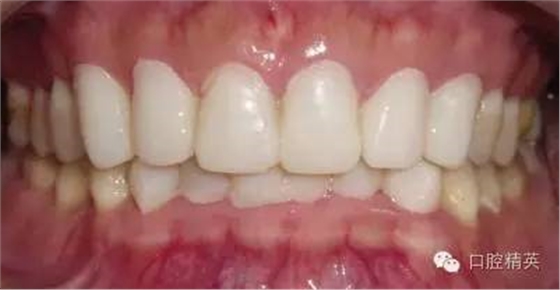

粘固后,對(duì)咬合關(guān)系進(jìn)行初步調(diào)整。三天后,復(fù)查,進(jìn)一步確認(rèn)咬合關(guān)系,必要時(shí)進(jìn)行調(diào)整(見圖12)。

LAVA 全瓷冠強(qiáng)度高,顏色自然,邊緣高度密合,切端可見半透明感,整體效果理想,與修復(fù)前(見圖1)相比取得了醫(yī)患均滿意的效果。